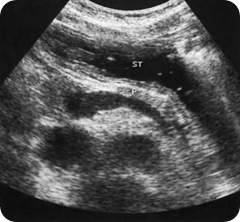

Ultrasound images Water in the stomach, ST, provides a window through which to view the pancreas